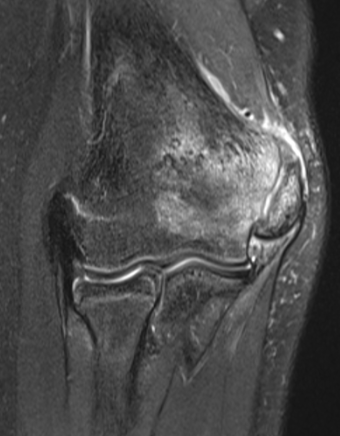

MRI

Edema around medial epicondyle

UCL injuries